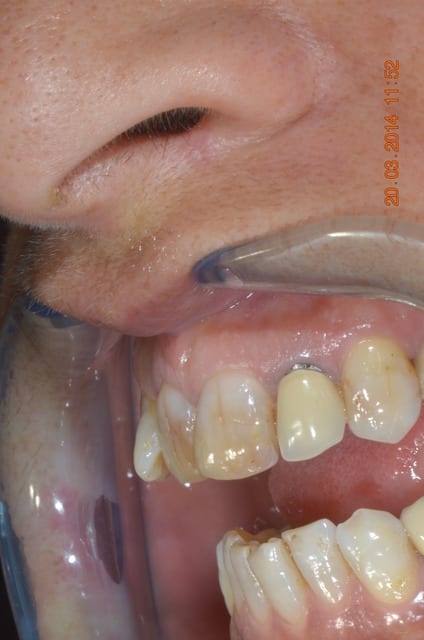

Allez, posé y'a 15 minutes. Collage multilink.

Belles préparations , attention par contre à ne pas trop " creuser" le congé (voir 22), ce qui entraîne une limite un peu pointue et fragilise la céramique.

> Belles préparations , attention par contre à ne pas trop " creuser" le congé

> (voir 22), ce qui entraîne une limite un peu pointue et fragilise la céramique.

-preps un peu agressives, j'étais du même avis en voyant le modèle, c'est pour ça que je les ai postées: comme ça c'est confirmé. Je vais avoir la main un peu plus légère sur les prochaines.

-par contre pour le congé 22 23 un peu creusé, d'anciennes CCM étaient présentes, je pense donc que c'était déjà le cas sur les preps antérieures.

-A noter, ça se voit mal sur les photos, que 11 12 13 sont des couronnes 3/4, la limite palatine se situe 3mm au-dessus de la gencive.